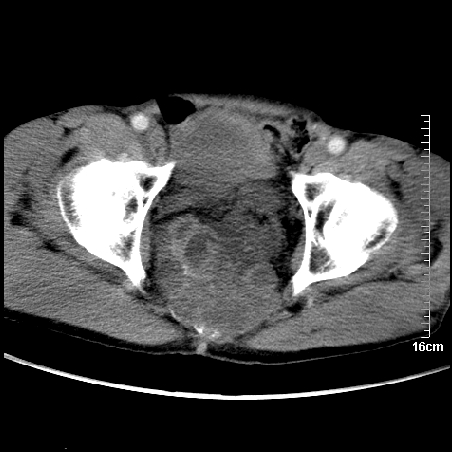

标题: CT16886:骶尾部占位:1.脊索瘤?2.巨细胞瘤? [打印本页]

标题: CT16886:骶尾部占位:1.脊索瘤?2.巨细胞瘤?

增强:

1、骶尾部巨大软组织肿块,部分骶尾骨以被软组织肿块代替,呈不规则侵蚀;病变突向盆腔内;增强扫描病变呈不均质强化;首先考虑脊索瘤。不支持的一点就是病变内无钙化。

2、发生于骶尾椎者须与骨巨细胞瘤鉴别,骨巨细胞瘤一般发在上疗骶椎,肿瘤内无钙化,一般无侵袭性生长的表现。